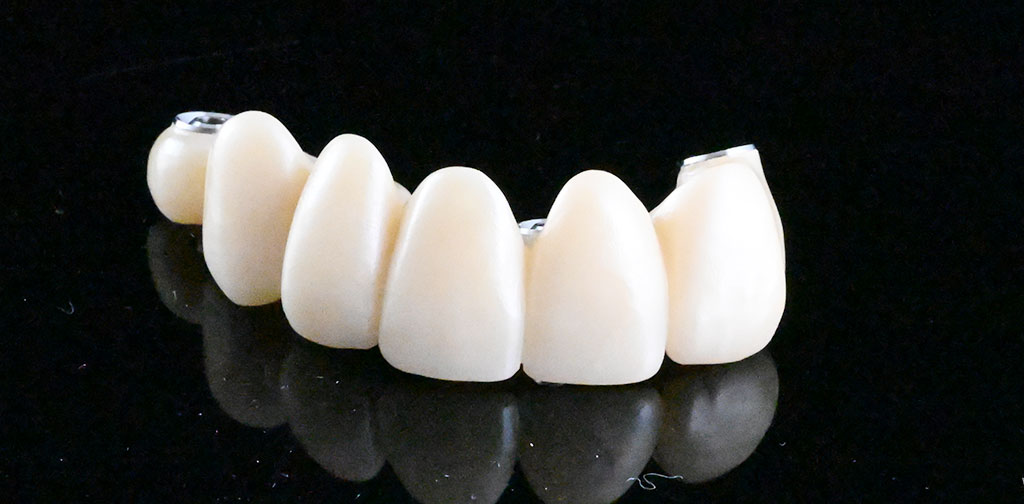

セットした上部構造

左上1,2番、右上4番インプラント治療

(右上1,2,3,4番、左上1,2番)インプラントブリッジ:110,000円/1本×3=330,000円(6本症例のうち、3本上記インプラント代に含む)